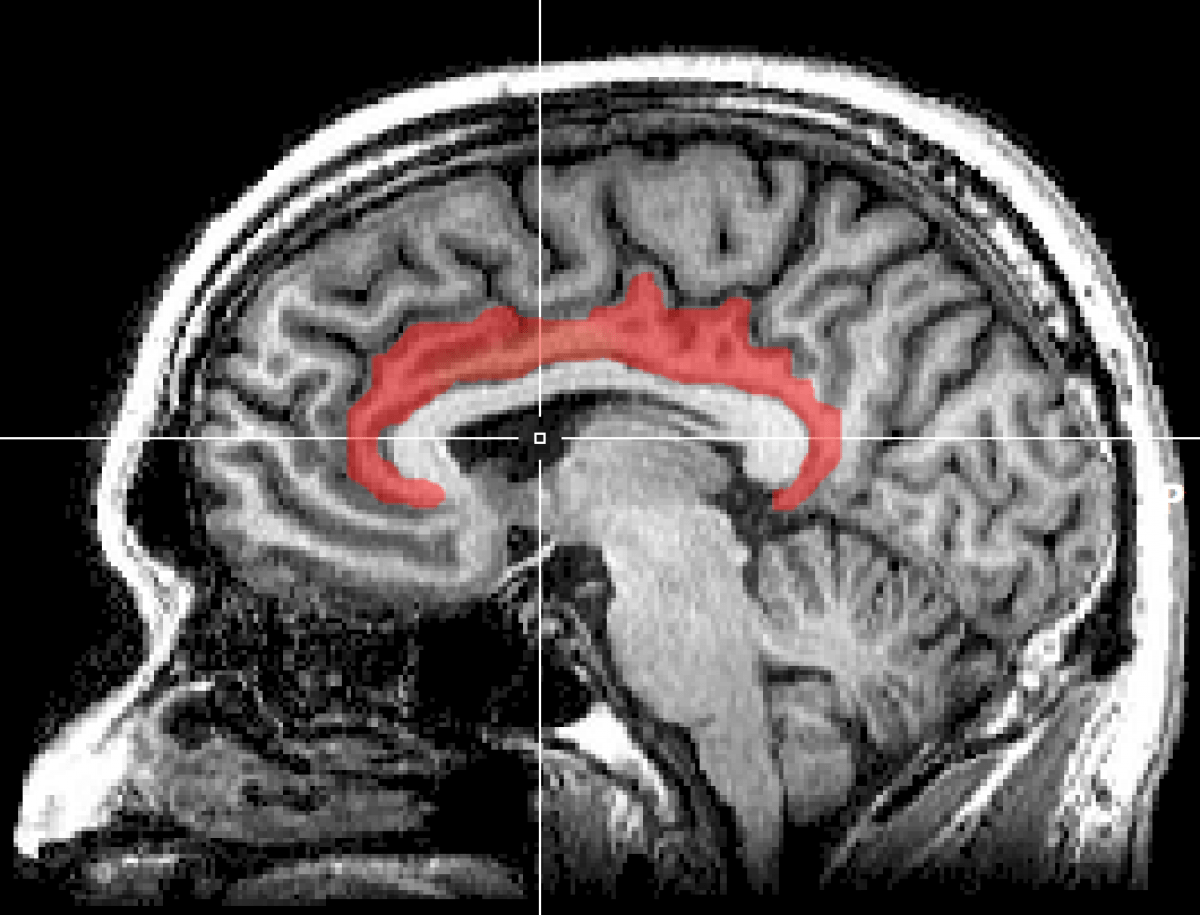

Mri Cingulate Cortex